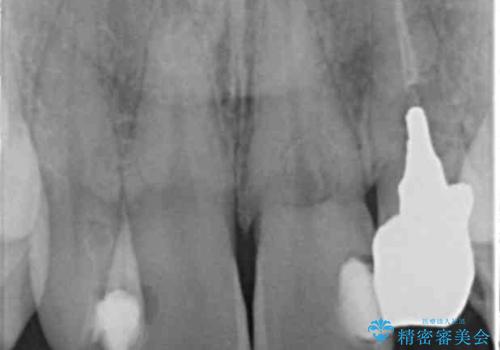

[ 歯ぐきを押すと痛む ] 根管治療の必要な前歯治療

![[ 歯ぐきを押すと痛む ] 根管治療の必要な前歯治療の症例 治療前](https://seimitsushinbi.jp/wp/wp-content/uploads/2021/10/c82595c07b1034d506ee9a41b2f43a37-500x350.jpg?v=1634264510)

![[ 歯ぐきを押すと痛む ] 根管治療の必要な前歯治療の症例 治療後](https://seimitsushinbi.jp/wp/wp-content/uploads/2021/10/5f5858ad0a0979b6f98bd8be1e57a5d6-500x350.jpg?v=1634264519)